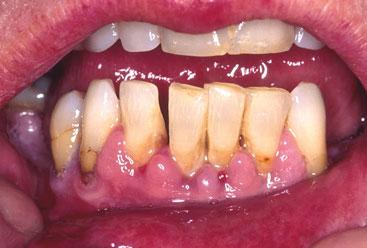

GINGIVAL ENLARGEMENT

The presence of plaque and resultant inflammation may lead to gum enlargement. It may also be induced by drugs — for example, phenytoin, ciclosporin and calcium-channel blockers (in this case amlodipine). In pregnancy, where there is plaque disease, gum change may occur. Systemic illness, e.g. vitamin C deficiency, leukaemia may be associated with gingival enlargement. Treatment requires intervention by a dental hygienist to remove plaque from below the gum line.